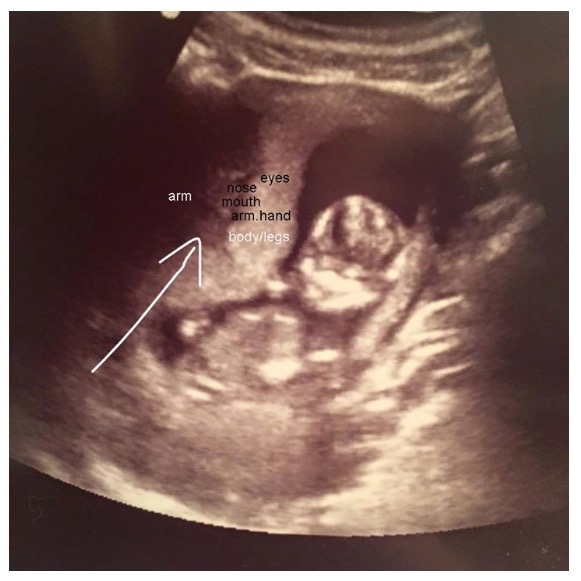

This is particularly true in the early months of pregnancy. However, there is a very small chance that a twin can be missed on a scan, particularly during early pregnancy. The pregnancy is outside the womb (an ectopic pregnancy) your obstetrician and midwives will need to do a series of blood tests. So i�ve been having ultrasounds every week since i discovered i was pregnant due to my history of previous miscarriages in my early 20�s, now i�m 34 years old, and yesterday i had my 8 week scan and there is a perfect yolk sac and the gestational sac has grown a good bit since my last scan six. This is how detailed a pregnan.

Even at eight weeks’ gestation, a trained sonographer can readily identify one or more embryonic sacs. Babies are not missed on ultrasound that far along. This is an effective way of down syndrome detection. I had an early (8 weeks) ultrasound and the doctor said she couldn�t rule out twins at this point. Could another baby really be hiding? It is too soon to see the baby on the scan.

Can a baby be missed on ultrasound finding out you’re expecting twins in most cases, if you’re expecting twins or more then you will find out as soon as you have your first ultrasound scan. Shaking my head in disgust. One developing baby can be almost like a shadow of the other and difficult to detect. This is particularly true in the early months of pregnancy. It’s not unheard of for a twin pregnancy to go undetected in early ultrasounds (say, around 10 weeks).

3.1% (a third of the suspected abnormal screening scans) showed a fetal anomaly. While you may have heard anecdotally of twins missed on ultrasound, experts agree that in modern uses of either vaginal or transabdominal ultrasound such an occurrence would be extremely unlikely. Can twins be missed at 7 week scan? Could another baby really be hiding? Heartbeats can be so in sync that it is hard to distinguish one from the other.